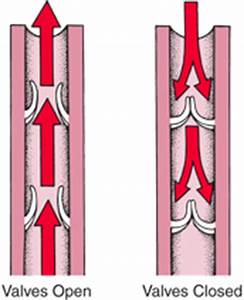

Image of Valves

Veins have the lowest pressure and need valves to ensure blood flows in the correct direction in the vessel (just like lymphatic vessel). As you can see from the graph, blood pressure and velocity drop rapidly as it enters the capillaries because the total vessel volume rapidly increases.This provides maximum time for exchange of materials between vessels and cells.